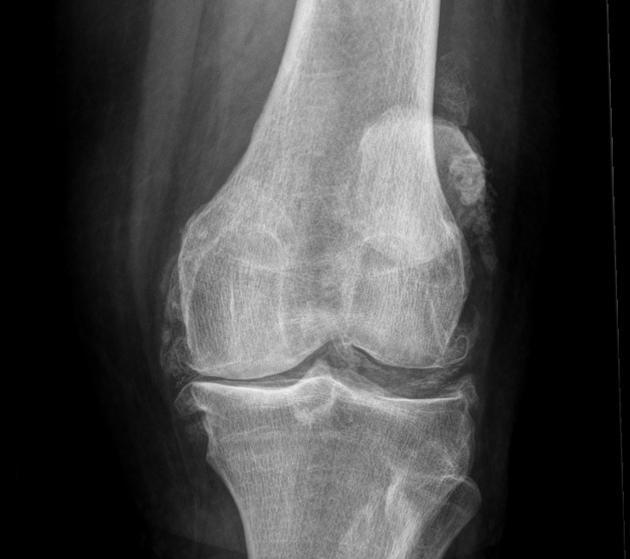

1/.膝関節:高齢者のしゃがむ&立っている困難で、多くの原因は、膝の変性、関節炎、滑膜炎、靭帯だけでなく、半月板の損傷によって引き起こされる。膝関節の変性では、冷たさの一定の年数の初期に現れ、階段を上る二重膝の弱さ、歩行が柔らかく再生され、後に現れた痛み、膨張、しゃがむ難しさの症状では、膝の脛骨プラットフォームであるため、顆間骨棘とギャップが広く、不均一に狭く、骨水腫、無菌性骨膜(滑膜炎)、半月板の摩耗や断裂、大腿四頭筋などの筋肉の緊張、靭帯損傷など。診断と鑑別は、血液検査、リウマチ4項目、抗環状シトルリン化ペプチド抗体検査、核磁気検査などで確認する。

関節の軟骨がすり減る程度が少なければ、患者は何も感じないが、軟骨のすり減りが深刻になるにつれて、すり減る範囲がどんどん大きくなり、すり減る厚みがどんどん大きくなり、関節が屈曲、伸展、活動する過程で、骨と骨の間の圧力が大きくなり、私たちの体は、骨と骨の間の関節にかかる圧力をよりよく軽減するために骨棘が現れ始め、骨が肥大化する。比較的小さな時間の誕生は、任意の症状を生成しませんが、より多くの大規模な、より多くの場合、患者の関節の機能に影響を与え、その結果、患者がしゃがむしゃがむしゃがむダウンすることはできませんしたい、脚を曲げたい正常な位置に曲げることはできません、一部の患者はまた、高齢者の上記の状況は非常に一般的である、我々は障害物をまっすぐ表示されます呼び出す変形性関節症は、65歳以上の50%に見られる。。

- X線検査の主な目的は、関節腔が著しく狭くなっているかどうかを判断することである。狭くなっている主な理由は、軟骨がかなり薄くなり、自然な関節空間が狭くなっているからです。また、高齢者の関節はレントゲンでよく判断できます。骨の形成が多いかどうか(骨棘)それが体のどの部分に特異的に形成されるのか、高齢者ではどのような機能に影響を及ぼすのか、また、高齢者ではどのような機能が低下するのか。オステオイドの形成と関節腔の狭小化は、変形性関節症における最も典型的な変化である。。